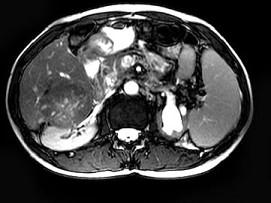

问题 男,65岁。右上腹部疼痛不适,乏力4月余。AFP升高。MRI如下图所示。应诊断为 ( )

选项 A、转移瘤 B、未见异常 C、胆管细胞癌 D、肝腺瘤 E、肝右叶肝细胞癌并门脉癌栓形成

答案 E